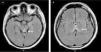

Varón de 23 años, con antecedentes de pancreatitis biliar hace un mes y colecistectomizado hace una semana, presenta historia de 2 días de fiebre, mareo, confusión y debilidad muscular marcada en miembros inferiores por lo que ingresa a planta de medicina interna. En la exploración física se observa signos de deshidratación y se descartó complicación posquirúrgica. Tomografía de cerebro y abdomen normal. Al día siguiente evoluciona con somnolencia, cuadriparesia, hiporreflexia seguido de estupor e inestabilidad hemodinámica por lo que ingresa a Unidad de Terapia Intensiva; se inició tratamiento empírico con meropenem y vancomicina. Se realiza resonancia magnética de cerebro que reveló lesiones hiperintensas en tronco cerebral, fórnix y tálamo bilateral (figs. 1 A y B, flechas blancas), sin desplazamiento de línea media. El diagnóstico diferencial incluyó vasculitis, herpes, tuberculosis y toxoplasmosis. El estudio citológico bioquímico de líquido cefalorraquídeo se mostró inespecífico y en estudio de biología molecular por PCR se detectó ARN del virus del Zika. Se inicia tratamiento inmunomodulador con inmunoglobulina humana (IgG), a los 5 días se realiza nueva resonancia magnética que evidencia progresión de lesiones a pedúnculos cerebrales y núcleos de la base (figs. 2 C y D, fechas blancas) seguido de disfunción orgánica múltiple y muerte.